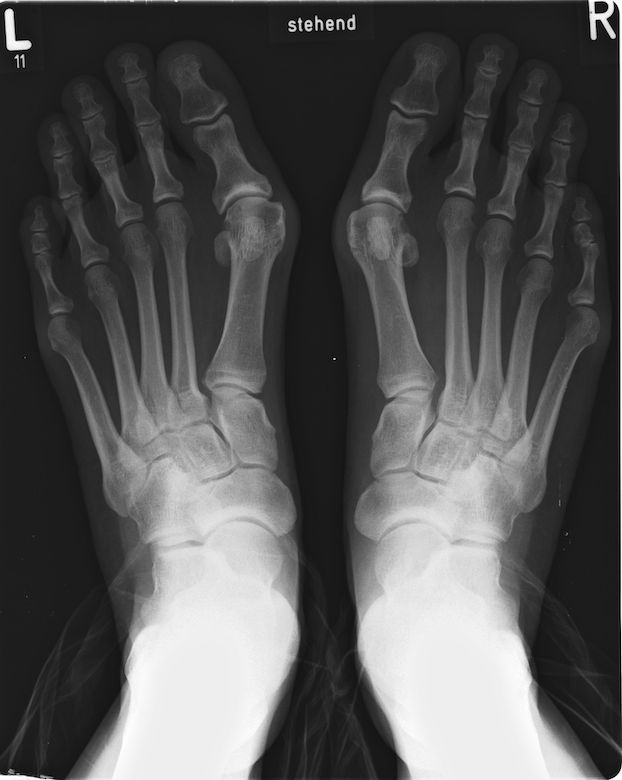

Když se palec u nohy naklání k ostatním prstům, dochází k rozšíření chodidla a vyčnívání kloubu palce z boku nohy. Toto nesprávné postavení ovlivňuje i ostatní prsty, vede k bolesti, necitlivosti, zánětům kůže, mozolům a kuřím okům, otokům a zarudnutí.

Může mít dokonce za následek i jiné deformace nohy, například kladívkové nebo drápovité prsty. Deformita, častěji se vyskytující u žen a obecně osob nad 65 let věku, postiženému ztěžuje nejen každodenní život, ale i hledání vhodné obuvi.

Hallux vagus je dnes jednou z nejběžnějších chorob nohou u lidí. Z evolučního hlediska to ale nedává smysl, přirozený výběr měl upřednostnit jedince s nohama, které se nedeformují. Proč k tomu tedy nedošlo?